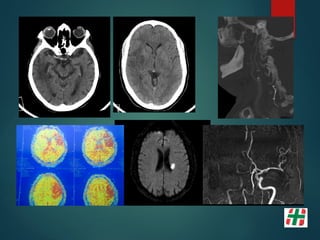

STROKE ISQUÉMICO AGUDO

Isquemia Cerebral

 Alteración en el aporte de oxígeno y nutrientes al

parénquima encefálico.

 80% de los Stroke en general.

 3er causa de muerte general.

 1er causa de morbilidad.

Tomografía Computada

 Signos Tempranos de Stroke:

◦ Signo de la cuerda.

◦ Borramiento del ribete insular.

◦ Borramiento - Asimetría de surcos.

◦ Falta de diferenciación de las sustancias gris-blanca a nivel de los

ganglios basales.

Tomografía Computada Resonancia Magnética

MULTIMODAL

Infarto Agudo – RM

 Inmediatos ---Vasos

• Ausencia del vacio de flujo

• Estasis en FLAIR. Refuerzo con Gd

• AngioRM : obstrucción / estenosis

 Perfusión: